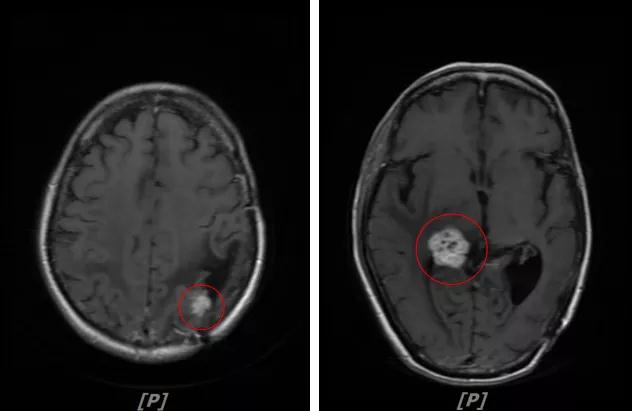

5. 病情第4次进展:2019年11月患者出现视野模糊等症状

头颅增强MR:左侧顶颞叶见片状T1WI低信号、T2WI高信号影,病灶大部信号接近脑脊液,增强后术区边缘左侧顶叶见结节状强化影,大小约10x8x11mm,较2019-03- 15MR老片大致相仿;右侧脑室三角区见结节样T1WI等低信号、T2WI不均匀稍高信号影,增强后不均匀明显强化,大小约24x18x20mm,较2019-03-15MR老片明显增大;两侧半卵圆区、侧脑室旁见较对称片状T1WI低信号、T2WI高信号影,增强后未见明显强化,较前片相仿;余脑室、脑池、脑沟大小形态可,中线结构向左偏移。

左顶颞叶转移瘤治疗后改变

右侧脑室三角区旁强化结节,较2019-03-15MR老片明显增大 左侧顶叶强化结节,较2019-03-15MR老片大致相仿

两侧脑室旁云絮状异常信号,考虑放疗后改变

患者三线治疗的PFS为14个月,2019年12月给四线治疗为“吡咯替尼+阿那曲唑”基础上联合曲妥珠单抗。

患者视野模糊等症状有所改善,继续定期复查。

6.病情第5次进展:2020年5年患者头痛等症状进一步加重

头颅增强MR:左侧顶叶皮层区见不规则片状T1WI低信号、T2WI高信号影,病灶大部信号接近脑脊液,增强后无强化,其边缘见结节样明显强化影,平扫近似等信号,大小约12x12mm,较2020-02-11MR老片略增大,左侧脑室三角区不均扩大;右侧颞叶-丘脑区见结节样T1WI等低信号、T2WI不均匀高低混杂信号影,增强后不均匀明显强化,大小约24x23x26mm,较前片增大,似见累及胼胝体压部;两侧半卵圆区、侧脑室旁、基底节区及右侧丘脑、颞叶见融合团片状T1WI低信号、T2WI及Flair高信号影,增强后未见明显强化,较前片相仿;余脑室、脑池、脑沟大小形态可,中线结构向左偏移。左侧乳突区见T2WI高信号影充填。

颅脑转移瘤治疗后观

左顶叶强化结节、右侧颞叶-丘脑区结节影:较前片增大

幕上脑白质融合异常信号:符合放疗后改变

患者四线解救治疗的PFS为5个月。2020年6月改用T-DM1方案治疗(恩美曲妥珠单抗,160mg,21d重复),同时改用依西美坦(25mg,qd)

患者头痛等症状明显好转,病灶持续缩小,继续定期复查。